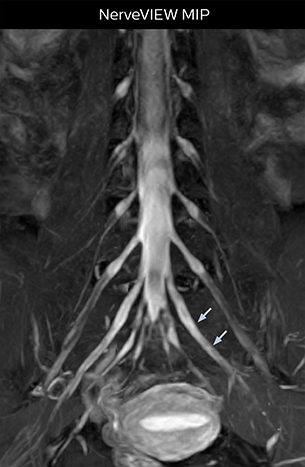

“In patients with lower extremity neurological symptoms, NerveVIEW helps us to determine the disease matching the patient’s symptoms by directly visualizing the nerves. We use the sequence mainly, when there is suspicion of intraforaminal stenosis, extraforaminal stenosis or lateral disc herniation, which is often based on routine T2- and T1-weighted images. Additionally, the excellent depiction of the course of nerves makes NerveVIEW a good navigator when applying treatment such as block therapy or surgery.”

The key concept in MR neurography, Dr. Yabuki stresses, is the ability to directly visualize spinal nerves, versus inferring the presence of pathology indirectly. “Before NerveVIEW, we estimated compression of the nerve by looking for the presence or absence of fat signal on other MR images,” he says.

“For example, in sagittal images, when the presence of fat is observed in the intervertebral foramen, it suggests that there is a margin around the nerve. Similarly, the absence of fat indicates that the nerve is being compressed. So, we used to deduce nerve compression indirectly. With NerveVIEW, however, we can observe the condition of the nerves directly, regardless of the presence or absence of fat. We always prefer such direct observation of anatomy over having to make an inference about it.”

“NerveVIEW is really useful for those cases where a nerve disorder is strongly suspected based on the clinical examination but our regular MRI images do not show any findings. These atypical herniations and spinal canal stenosis, occurring in 5% to 15% of the total lumbar herniation/stenosis cases are our main target when using NerveVIEW,” says Dr. Yabuki.

“Although symptoms of typical disc herniation and atypical hernia are very similar, the actual site of herniation is different. It is therefore important to characterize the nerve’s condition both inside and outside of the intervertebral foramina.

According to Tanji, methods such as ProSet FFE, STIR or 3D VISTA are anatomically nonselective because background signals, for instance from blood vessels, often interfere with nerves, which hampers evaluation of details, especially at the peripheral side of the nerves.

“The intra-luminal signal of veins, especially around the intervertebral space, can be suppressed well with NerveVIEW. As a result, we can easily observe the detailed nerve structure around the posterior ganglion,” he says. “This is why we use 3D NerveVIEW for intraforaminal stenosis and extraforaminal stenosis/herniation (lateral disc herniation). On the other hand, if herniation is suspected to exist inside the dorsal root ganglion (DRG), balanced TFE or ProSet-FFE is applied. NerveVIEW is not suitable for evaluating the median type of herniation.”

Because the obtained NerveVIEW images often exhibit a high signal in the intervertebral discs, we use partial MIP images to eliminate such intervertebral disc high signals. MIP image generation is based on the  center of the coronal stack, and RAO (right anterior oblique) and LAO (left anterior oblique) images rotated in the range of 45 degrees are used for diagnosis.